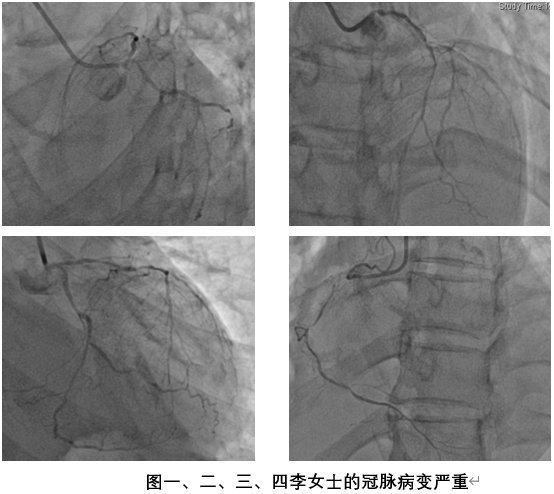

做完冠脉造影后,结果显示左主干严重狭窄合并三根主要冠脉多处严重狭窄,对于这类患者来说,冠脉搭桥手术是治疗的最优解。超声心动图还提示李女士的二尖瓣存在中-大量返流,心脏的收缩功能受损严重,心脏射血分数在30%左右。心脏病变的解除迫在眉睫,每一秒都危机四伏,经过家属及本人同意,李女士转入了心脏外科沈冬焱团队进行术前准备。